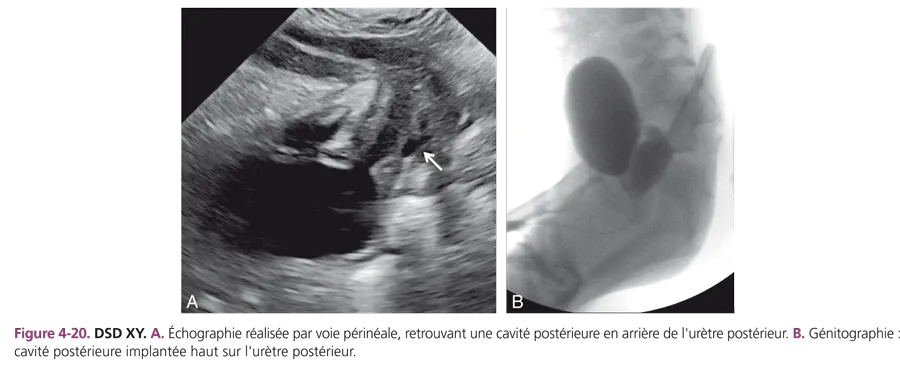

Elles représentent environ 45 % des états intersexuels. Ce sont des garçons, au caryotype normal 46XY, présentant des testicules normaux souvent palpés dans les bourrelets labioscrotaux et dont la masculinisation du sinus urogénital est insuffisante. Le taux sanguin de testostérone est normal. L’échographie montre l’absence de structure utérine puisqu’elle a régressé sous l’effet de l’hormone antimüllérienne normale. La génitographie révèle souvent la présence d’une cavité postérieure qui témoigne du défaut de masculinisation du sinus urogénital. L’insensibilité aux androgènes est l’étiologie principale, recherchée par l’étude des fibroblastes de la peau périnéale biopsiée. L’insensibilité est liée à un trouble de réceptivité aux androgènes par anomalie quantitative ou qualitative des récepteurs dans les tissus cibles, souvent difficile à mettre en évidence. Sa forme complète réalise le syndrome de féminisation testiculaire. Dans les formes incomplètes, le trouble de la différenciation sexuelle est plus ou moins sévère, posant de difficiles problèmes de choix du sexe (fig. 4-20) car l’insensibilité persistera à la période pubertaire.